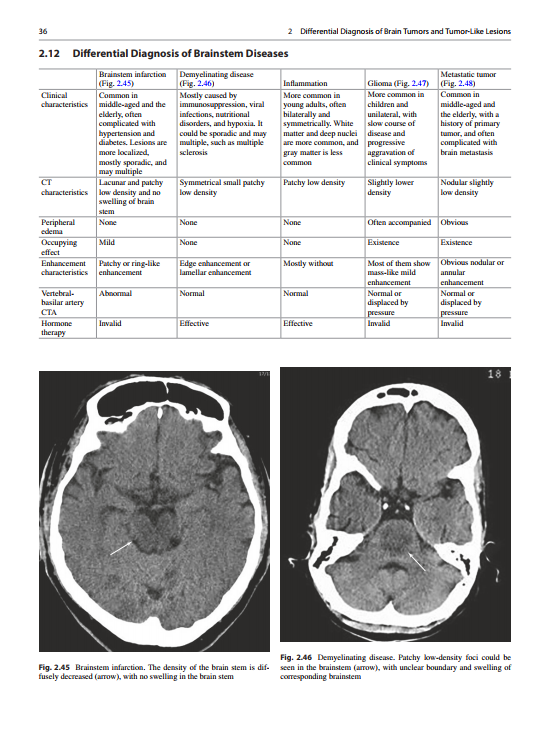

Description

Atlas of Differential Diagnosis CT (by Guoguang Fan)

Aiming to equip readers with the knowledge required for accurate and timely diagnosis, this book presents illustrative cases that address a broad spectrum of clinical problems, including frequent, uncommon and rare diseases of brain, head and neck, spine, musculoskeletal system, chest and abdomen. To make readers understand easily, tips in differential diagnosis are summarized in the table, accompanying with typical images and key teaching points. It will be a valuable resource for diagnostic radiologists, residents, fellows, and related clinical doctors.